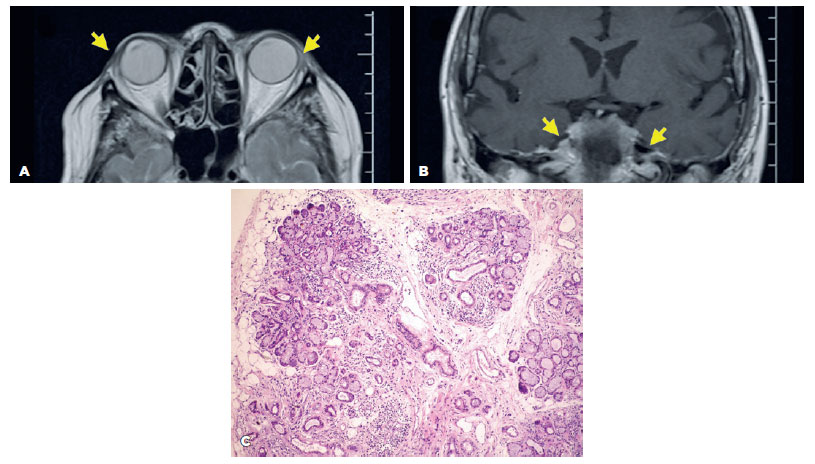

A 24-year-old white woman presented with DES over the last three years without dry mouth. She reported no comorbidities and no use of medications, except for treatment of acne with RA at 14 and 20 years of age, lasting for six months on both occasions. The ophthalmological examination demonstrated a visual acuity of 1.0 in both eyes (OU); a tear film break-up time (TFBUT) of 2 s in the right eye (OD) and 1 sin the left eye (OS); a grade 5 corneal fluorescein staining in OD and grade 3 in OS, with filamentary keratitis; and a Schirmer test (ST) showed absent tear flow (zero mm) in OU. Moderate MG dysfunction (MGD) with less than 30% of gland drop out, light expressibility, and cloudy oil secretion were observed. The ocular surface disease index (OSDI) was 70.45%, and the whole saliva flow was 0.13 ml/min (normal value, >0.1 ml/min). Serological tests for autoimmune and viral systemic diseases, including anti-Ro/SSA, anti-La/SSB, anti-dsDNA, anti-SM, anti-RNP, antinuclear antibody (ANA), and rheumatoid factor, were negative. A biopsy of her minor lip SG revealed a focus score of zero. MRI revealed the absence of the LG bilaterally (Figure 1A). The average normal LG volume is 0,580 cm3.

11-fig01tb.jpg)

A 77-year-old female presented with DES for five years, which had worsened 12 months before the visit and was attributed to emotional problems. She was using artificial tears and lacrimal punctal plug occlusion. She mentioned a diagnosis of prolactinoma 30 years prior to this visit, which manifested initially with galactorrhea, further confirmed by laboratory and imaging exams. She had been using carbegoline since that diagnosis. Thyroidectomy and systemic arterial hypertension were treated with Puran T4 and hydroclortiazide, respectively. Her physical exam was not remarkable. Her ocular exam was positive for mild bilateral blepharospasm and mild punctate keratitis. The TFBUT was 30 s and the ST was 5 mm OU. Mild MGD with 20% of gland drop out, light expressibility, and cloudy oil secretion were observed. No changes in the eyelid margin, mucocutaneous junction, or gland orifices were observed. The whole salivary flow was 0.02 ml/min. The laboratory exams were normal, including the prolactin and thyroid stimulating hormone (TSH) levels. The anti-Ro/SSA, anti-La/SSB levels were negative. A biopsy of the lip SG revealed moderate acinar atrophy and mild diffuse lymphocytic infiltration, but no focus score. The MRI analysis revea led bilateral atrophy of the LG and the parotid gland (Figure 3). Moreover, a biopsy of the labial SG showed tissue hypotrophy and diffuse lymphocytic infiltration, but not the typical signs of SS, which are foci of lymphocytic infiltration (Figure 3C).

11-fig03tb.jpg)